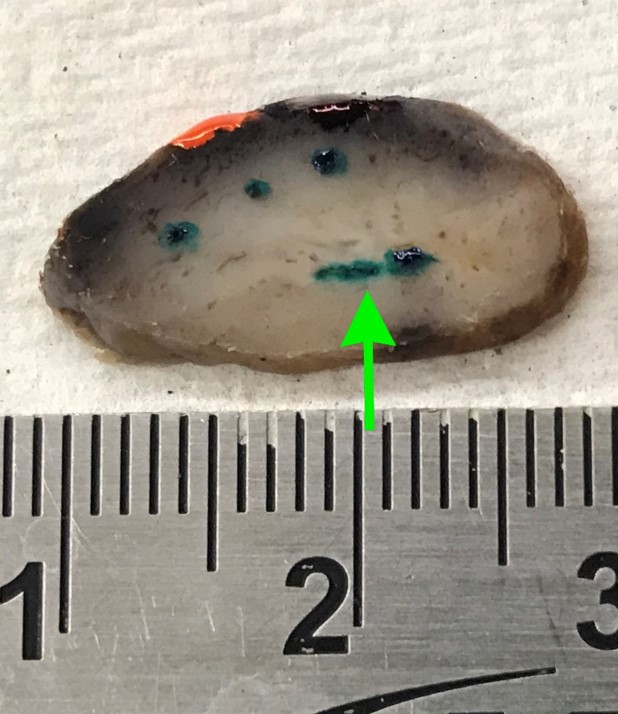

Gross description

- Polypoid firm mass

- Color varies from yellow to dark red or black, depending on the extent of intraoperative hemorrhage

Gross images